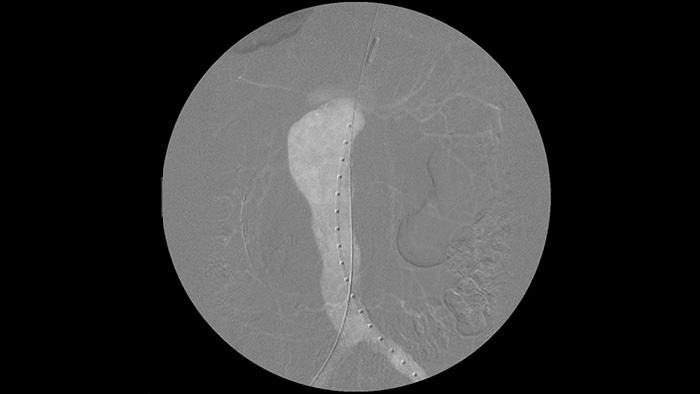

Met de mobiele C-boog van Philips Zenition verkrijgt dr. Vila uitstekende beelden van hoge kwaliteit, waardoor hij de meeste vasculaire procedures kan uitvoeren met een lage dosisinstelling.

Met de Zenition is onze DSA-beeldkwaliteit aanzienlijk verbeterd. Het beeld is niet korrelig, maar heel duidelijk.

Ramon Vila Coll

Arts in het universitaire ziekenhuis Bellvitge in Barcelona

Digitale subtractieangiografie (DSA) wordt bij interventionele vasculaire procedures gebruikt om bloedvaten duidelijk te visualiseren door structuren die de zichtbaarheid van bloedvaten kunnen beperken te verwijderen. Roadmap-fluoroscopie overlapt eerder verkregen subtractiecontrastbeelden op live fluoroscopie, zodat u het instrument kunt volgen zonder opnieuw contrastmiddel te injecteren.

Superieure beeldkwaliteit en dosiscontrole van Zenition

Philips DoseWise Zenition is een unieke combinatie van technieken, programma's en praktijken, ingebouwd in onze Zenition mobiele C-boogsystemen, die tijdens elke toepassing klinisch relevante beeldkwaliteit bieden terwijl de dosis efficiënt wordt beheerd.

Voerdraden zijn gemakkelijker te zien dan bij ons oude systeem. U ziet nu de punt en de hoek van de draad die rondgaat, zelfs bij draden van 0,014 inch.

Dat komt doordat Zenition metaal en beweging compenseert.